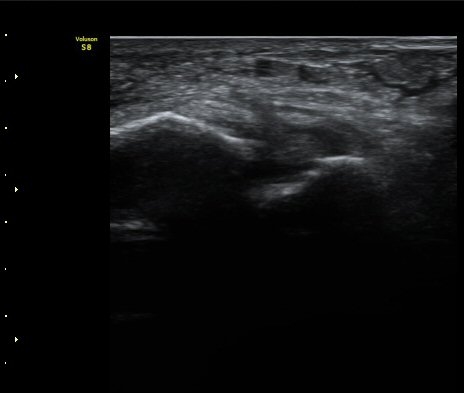

Àü°Å°ñºñ°ñÀδë Á¾´Ü¸é°Ë»ç»ó Àδë ÀδëÀÇ Àú¿¡ÄÚ ºÎÁ¾°ú(±×¸² 3)

ºñ°ñºÎÂøºÎ ¿¬°á¼º ¼Ò½ÇÀÌ °üÂûµÈ´Ù(±×¸² 4).

±×¸²3) Àü°Å°ñºñ°ñÀδë Á¾´Ü¸é°Ë»ç

±×¸²4) Àü°Å°ñºñ°ñÀδë Á¾´Ü¸é°Ë»ç